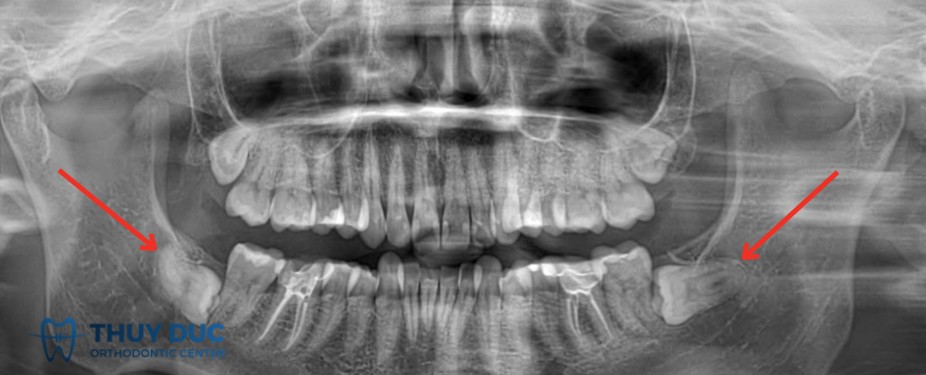

Vì vậy, phương pháp chẩn đoán chính xác nhất là chụp X-quang (thường là phim panorama hoặc phim cận chóp). Trên thực tế, rất nhiều bệnh nhân chỉ phát hiện mình có răng mọc ngầm khi đi khám và chụp phim để điều trị một vấn đề khác, ví dụ sâu răng, viêm nha chu hoặc chuẩn bị niềng răng.

2.1 Răng khôn mọc ngầm

Răng khôn là răng mọc cuối cùng trên cung hàm, thường xuất hiện ở độ tuổi 18-25. Do mọc muộn, cung hàm thường không còn đủ khoảng trống, khiến răng khôn dễ bị kẹt trong xương hoặc mọc lệch. Răng khôn mọc ngầm có thể gây đau, viêm, sâu răng lân cận vàđôi khi hình thành nang xương. Đây là loại răng mọc ngầm phổ biến nhất.